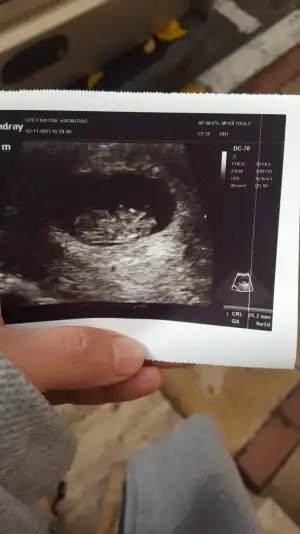

Tatlı yedim gitmeden çocuğum resmen halay çekiyordu🎈🙏😍😘😘 bunu buldum

Eklentiler

• IMG-20211103-WA0000.webp

IMG-20211103-WA0000.webp

28,6 KB · Görüntüleme: 57